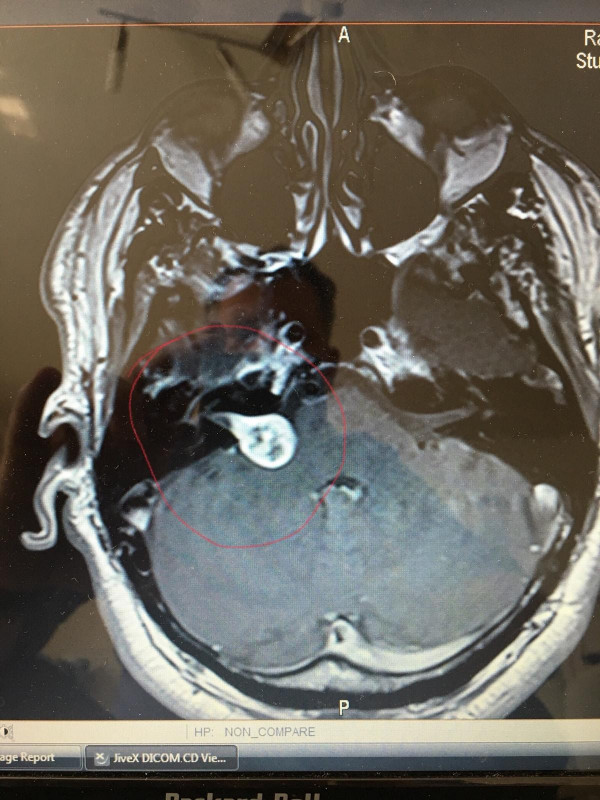

Der letzte große Schlag gegen mein Comeback was leider ein Hirntumor. Aber aktuell, ca. ein Jahr nach meiner OP ist alles gut.

49144903_10213041894304305_2463872138981933056_o.jpg

48944717_10213041893984297_4858891476853063680_o.jpg

Warum ich darauf eingehe, dieser Tumor war auch der Grund, warum ich aufgehört hatte. Mir ging es damals sehr schlecht und ich wusste nicht warum. Hatte kaum die Kraft einen Turn auf dem Motorrad zu sitzen und es wurde gefährlich. Also habe ich es gelassen als noch andere Dinge dazu kamen. Erst Jahre später, wurden von den Ärzten der Tumor und der Grund für meinen körperlichen Abbau bekannt. Heute geht es mir gut!